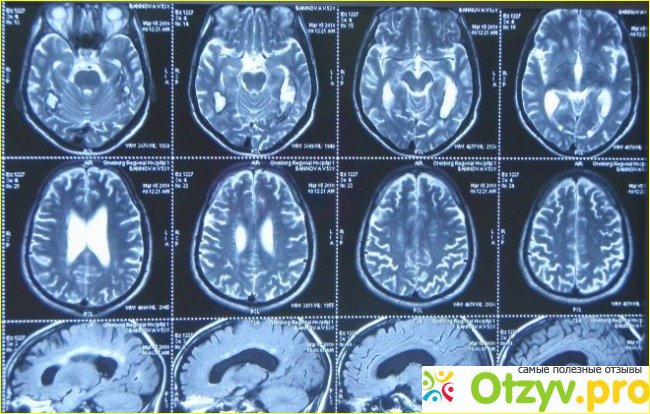

Очень удобный график работы медицинского центра, поскольку он работает ежедневно и без выходных с восьми часов утра и аж до девяти часов вечера (с 8-00 до 21-00). Здесь вам сделают качественное и быстрое обследование вашего позвоночника, головы, суставов. Как всем уже давно известно, мрт-это магнитно-резонансная томография, с помощью которой можно проводить исследования внутренних органов и тканей человеческого организма и это достаточно сложный метод, поскольку проводить его сможет не каждый врач и для этого нужно сложное и непременно качественное оборудование.